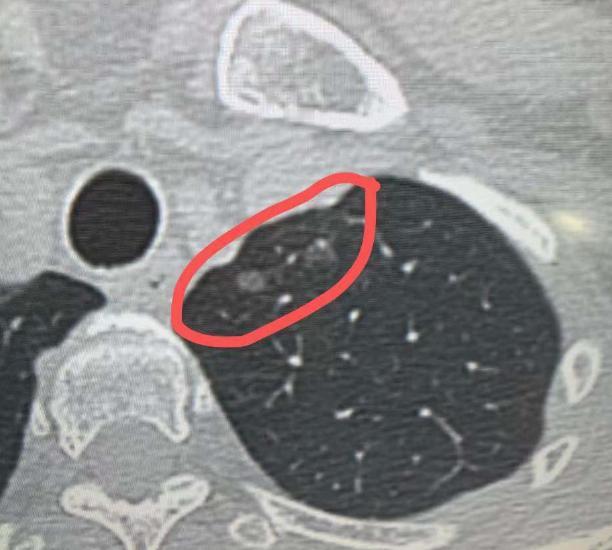

4mm磨玻璃结节,术后确诊肺微浸润癌?不少朋友查出几毫米的肺磨玻璃结节,还听说可能是原位癌、微浸润癌,就急着来找我,反复要求尽快手术切除,生怕耽误病情。 其实大家有这种焦虑情绪完全能理解,但对于小于5mm的肺微小结节,诊疗原则并不是一发现就切。 哪怕从影像学形态上高度怀疑是原位癌或微浸润癌,只要经过定期随访没有明显变化,单纯随访观察就足够安全,没必要盲目手术。 很多人会疑惑,既然都定性为“癌”了,为什么还能放任不管? 核心还是要权衡治疗收益和肺功能损伤。肺是人体重要的呼吸器官,每一部分肺组织都有其功能,为了一个几毫米的微小病灶,就切除周围大片正常肺组织,反而会影响后续呼吸功能,得不偿失。 尤其是这类惰性病灶,生长速度极其缓慢,长期随访无变化的情况下,不会对健康造成威胁,持续观察反而更稳妥。 也有患者跟我说,看我之前也做过4mm、5mm的肺结节手术,为什么自己的小结节就不建议切? 这里要明确,5mm以下结节是否手术,关键看切除操作对肺功能的损伤程度,不能一概而论。 手术决策需要结合结节位置、数量、患者整体情况综合判断,不是只看结节大小。 我之前接诊过一位60多岁的患者,左肺长了多个磨玻璃结节,其中左下肺背段的结节直径达1.5cm,不仅体积大,位置也比较表浅,适合手术切除,于是为她制定了左下肺段切除手术方案。 同时检查发现,她左上肺还有两个纯磨玻璃结节,分别是4mm和5mm,且都靠近肺外周,切除时仅需少量剥离周围肺组织,对肺功能影响极小。 最终手术中,我们在完成左下肺结节切除的同时,一并将这两个小结节切除,一次手术解决了三个病灶。术后冰冻病理结果显示,这两个小结节均为微浸润癌。 之所以一起切除,是因为患者本身就要接受左肺手术,在肺损伤可控的前提下,顺带清除同侧可疑恶性结节,既能避免后续二次手术,也能彻底消除患者顾虑。 总而言之,对于肺多发结节,手术决策的核心是平衡治疗效果与肺功能保护。单侧肺内若存在多个可疑恶性结节,在主病灶需要手术、且小结节切除对肺损伤较小的情况下,会尽量在一次手术中完整切除,最大程度保障患者健康。 但对于孤立的5mm以下微小结节,只要随访稳定,就无需过度焦虑,定期复查即可。[玫瑰][作揖]